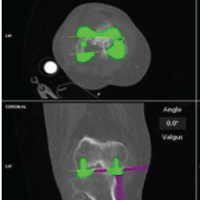

A representative example of Case 1 is illustrated in Figures 1–6. The preoperative radiograph is shown in Figure 1, while Figure 2 demonstrates the MRI findings confirming avascular necrosis of the lunate. Figures 3–5 depict the immediate postoperative radiographs and sequential follow-up images up to 1 year. Figure 6 shows the final clinical photograph, demonstrating a good functional outcome.

Figure 4: At 6 months follow-up, anteroposterior and lateral radiographs demonstrated stable fixation with maintained reduction, effective lunate unloading, and satisfactory evidence of healing with bony union. Clinically, the patient reported significant pain relief and improvement in wrist function.

Figure 5: Follow-up radiographs at 12 months (anteroposterior and lateral views) demonstrate good fixation, evidence of lunate unloading, and satisfactory healing with bony union.

Figure 6: At 12-month follow-up, the patient demonstrated well-preserved wrist function, with extension of 65° and flexion of 60°, and grip strength reaching 80% of the contralateral side. Radiographs confirmed stable fixation, effective lunate unloading, and complete bony union, correlating with the excellent clinical recovery.